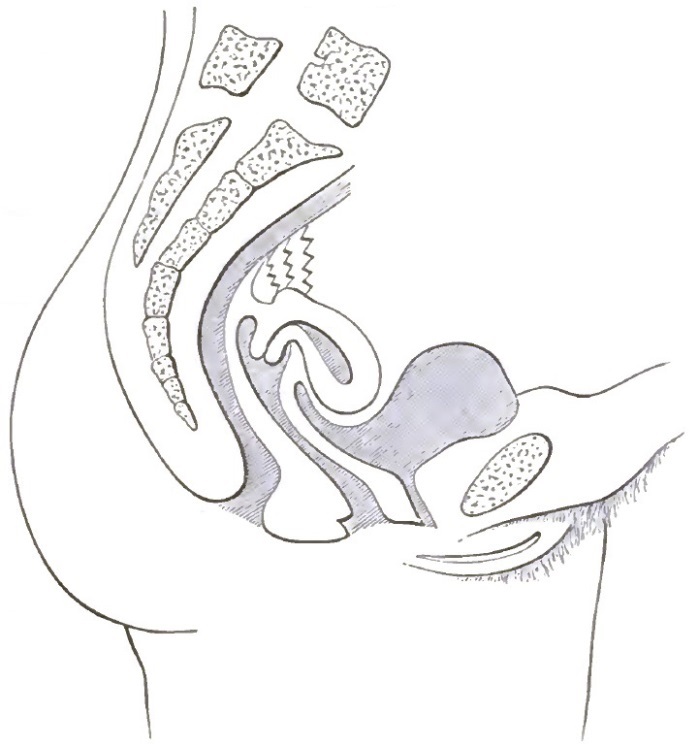

| 4. | SHOWING EXTREME DESCENT OF THE UTERUS AND OF THE PELVIC FLOOR, AND THE HERNIAL CHARACTER OF THE LESION |